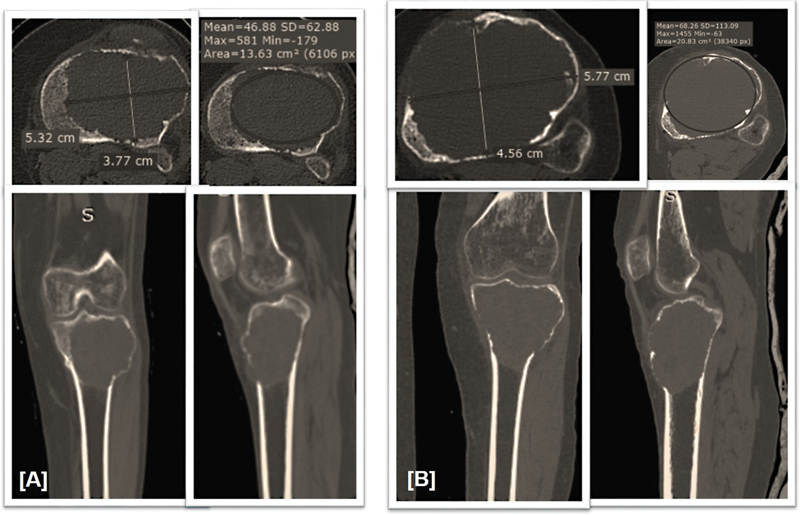

The patient demographic data, site and side of the lesion and the duration of symptoms was assessed at the time of biopsy. Clinical, radiological, and histological assessment was done at the time of biopsy, followed by evaluation by the same parameters after the completion of interferons alfa-2b. Clinical assessment was done by the size of swelling, consistency of swelling as soft, firm, and hard, and pain score in the form of a Visual Analog Scale (VAS) from 0 to 10.[17] Radiological assessment was done with a plain radiograph, CT scan, and MRI. In the plain anteroposterior radiograph, the size of the lesion, the border of the lesion (Campanacci grading),[10] marginal sclerosis as an increase in opacity on a margin of radiolucent lesion, and neocortex formation were assessed ([Supplementary Fig. S1], available in the online version only). CT scan and MRI were performed where the longest diameter in the axial view in the CT scan and MRI was used in the pretherapy and posttherapy period, and the reduction in %-of the size and increase in %-of density was assessed ([Figs. 1]

| Figure 2: (A) Representative image of computed tomography (CT) scan of patient with giant cell tumor (GCT) in the proximal tibia. (A) Pretherapy and (B) posttherapy, where the longest diameter in the axial view used to compare the reduction in %-of the size and increase in %- of density.

%-reduction in size (%S): The %-reduction in size (%S) was calculated as:

%S = longest diameter pretherapy – longest diameter posttherapy × 100.18

Longest diameter pretherapy: The %-increase in the density (%D) was assessed as:

%D= (pretherapy density) – (posttherapy density) × 100.19

Pretherapy Density

Size and density were calculated with the help of Radiant DICOM software. On the Radiant DICOM in the axial view of the involved segment, an ellipse was measured, and the mean density of the tumor was measured and calculated. The assessment criterion used was: inverse Choi density/size criteria (ICDS)[20] and Response Evaluation Criteria in Solid Tumor (RECIST).[21]

| Figure 2: (A) Representative image of computed tomography (CT) scan of patient with giant cell tumor (GCT) in the proximal tibia. (A) Pretherapy and (B) posttherapy, where the longest diameter in the axial view used to compare the reduction in % of the size and increase in % of density.